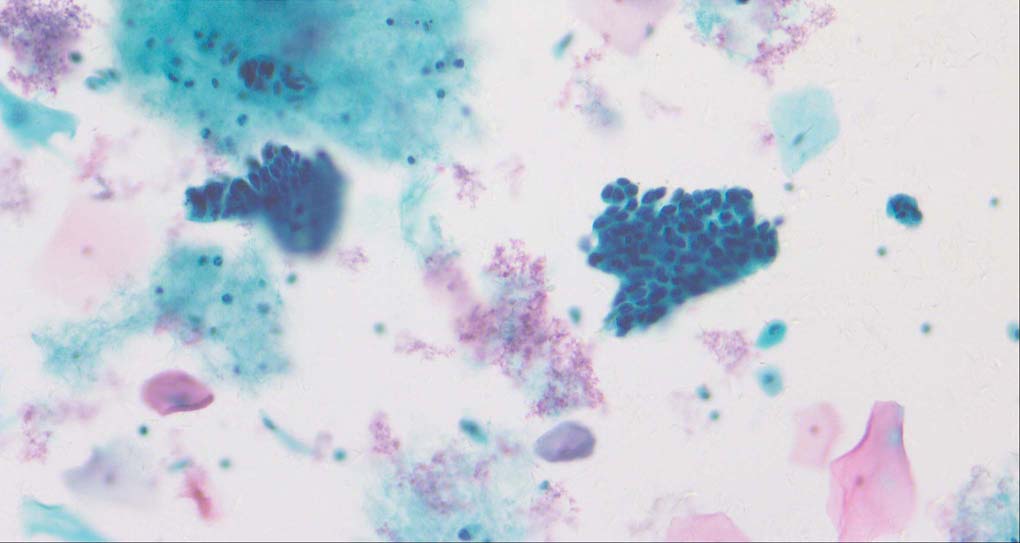

A good image fusion method should contain the following properties. First, it preserves both the details of small size objects and the integrity information of large size objects in the fused image, even in the case of the size of the interested objects varying largely in the image. For example, the cervical cell images from the microscope contain both small size isolated cells and large size agglomerates, which are both useful for cervical cytology [5]. Second, it should be efficient enough to handle large-scale data. For instance, it needs to process thousands of fields of view (FoV) in an acceptable time for the whole slide scanning in digital cytopathology [6], which requires to fuse a series of high resolution images captured at each FoV in a very efficient way. Third, it does not produce obvious artifacts. Despite being studied extensively, to our best knowledge, existing fusion methods may not meet these requirements simultaneously.

To demonstrate the effectiveness and efficiency of the proposed image fusion method , we conduct a set of comparative experiments on three image datasets. The first is composed by 8 pairs of multi-modal medical images and the second one contains 15 pairs of multi-focus gray or color natural images. These two datasets are often used in many related papers and some examples are shown in Figure 3(a) and Figure 3(b). The third one is a new multi-focus cervical cell image dataset collected by ourselves, which consists of 15 groups of color images and each group contains a series of multi-focus cervix cell images with size of or , etc. Some source examples are shown in Figure 3(c). Our source code implemented in C++ along with the new multi-focus cervical cell image dataset is available online.

Figure 9, Figure 10 and Figure 11 show the comparative fused results of the multi-focus cell images shown in Figure 3(c). For clarity, we also present a closeup view in the right-bottom of each sub-picture in Figure 9 and Figure 10. As shown in the close-up views of Figure 9, the fused images based on DSIFT, IM, MWGF and BF methods are extremely blurred in the boundary and fail to keep the details of cell nucleus. Furthermore, the DTCWT and NSCT based methods produce halo artifacts in the fused images, while GFF and CNN based methods fail to preserve the small cell nucleus. LP-SR based method nearly works fine which keeps the most of the details of the small size cells, but the integrity of the clustered large size cells is damaged. Fortunately, in our proposed method, the integrity of the clustered large size cells is preserved and most of the isolated small size cells are maintained from the original images, which demonstrates the best visual quality.

Similarly, as shown in the close-up views of Figure 10, the fused images from DSIFT, IM, MWGF and BF are blurred and lose some nucleus details, while the results from DTCWT, GFF, CNN and NSCT produce halo artifacts. LP-SR based method can keep details well but also produces halo artifacts and other noise. Our method can preserve the focused areas of different source images well without introducing any artifacts. For the example illustrated in Figure 11, the fused images generated by DSIFT, DTCWT, IM and NSCT all fail to preserve the focused areas of different source images and result in extremely blurred images. The GFF, CNN, MWGF and BF based method introduces a lot of color distortion of the nucleus regions and the obvious halo artifact. The result of LP-SR based method is close to the one of our method but introduces some odd color distortion. Again, our method produces fused image which can preserve the focused areas of different source images well without introducing any artifacts.